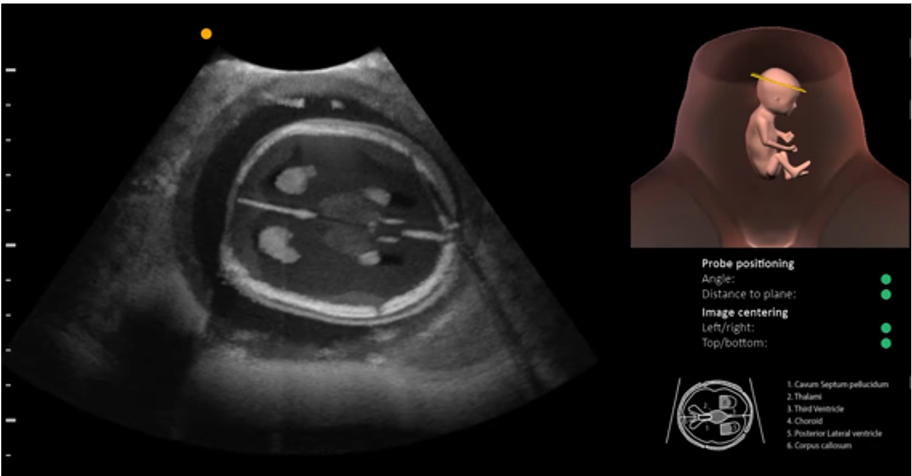

Ultrasound physics Ultrasound physics